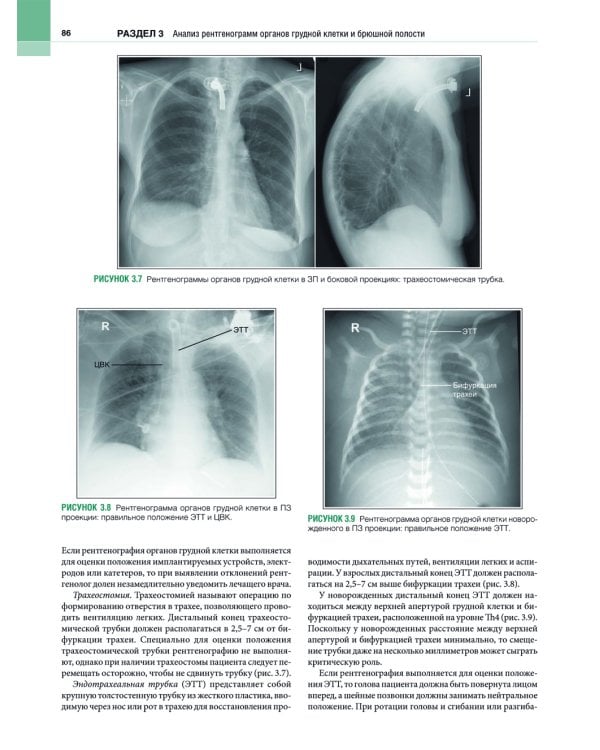

В этом практическом руководстве описаны основные методики выполнения рентгенографии и принципы анализа качества рентгенограмм, стандартные технические параметры исследования, а также варианты укладки и способы их коррекции. Особое внимание уделено базовым принципам получения и цифровой обработки изображений. Для каждой рентгенологической методики приведены фотографии правильной укладки пациента, варианты укладки в нестандартных ситуациях и при определенных патологических состояниях, а также таблицы с сопоставлением вариантов укладки, примеры определения центрального луча или приемника изображения, рисунки и фотографии костных препаратов и условного пациента, позволяющие точнее отобразить взаимное расположение анатомических структур, если проекционное искажение затрудняет интерпретацию рентгенограмм. Издание содержит более 1500 иллюстраций. Книга предназначена для рентгенологов.| Издательство | ИЗД.ПАНФИЛОВА |